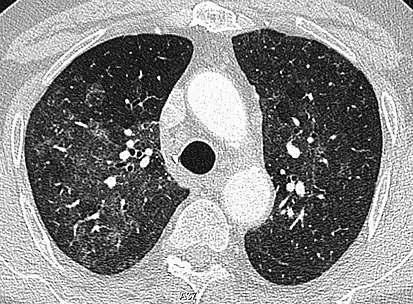

CT image showing diffuse GGOs throughout both lungs. An abscess is also noted in the right lung (screen left). - Adenocarcinoma in situ of the lung